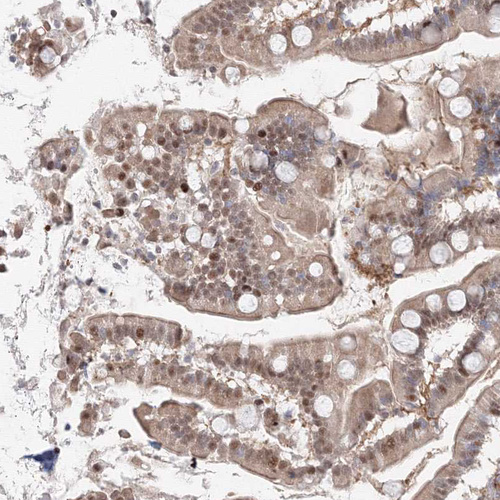

Immunohistochemical staining of human small intestine shows strong nuclear positivity in glandular cells.